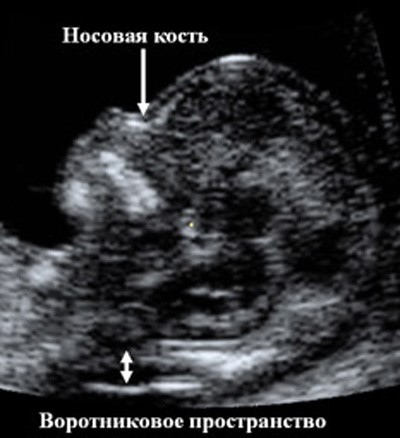

С 11 по 13 неделю можно выявить ультразвуковые маркеры (признаки) хромосомной патологии плода – увеличение толщины воротникового пространства плода и отсутствие у него носовой кости при проведении УЗИ.

Толщина воротникового пространства плода (ТВП) – это размер участка между кожей плода и мягкими тканями, окружающими шейный отдел позвоночника. Воротниковое пространство выявляется у плодов как в норме, так и при хромосомных заболеваниях (например, болезни Дауна), но для плодов с хромосомными заболеваниями характерно увеличение толщины воротникового пространства более 2,5мм. Воротниковое пространство у всех плодов самопроизвольно исчезает после 14 недель беременности, поэтому очень важно пройти исследование с 11 по 13 неделю беременности, когда его можно измерить.

Носовая кость в норме определяется при УЗИ с 10 недели беременности. У плодов с хромосомной патологией процессы окостенения происходят позже, поэтому отсутствие носовой кости при ультразвуковом исследовании в эти сроки может являться признаком хромосомной патологии плода.

Для оценки этих признаков врач должен обладать высокой квалификацией, так как получение необходимых ракурсов плода в ранние сроки беременности требует опыта и технических навыков. Для измерения ТВП необходимо получить такое изображение:

На фото УЗИ беременной видна только голова и верхняя часть туловища плода, четко виден профиль, носовая кость и ТВП. Достаточно часто можно увидеть такие некорректные изображения:

Схема измерения толщины воротникового пространства